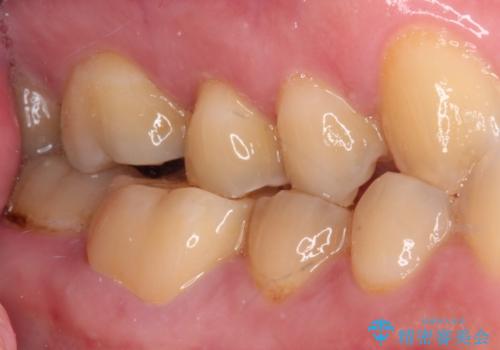

精度の高いセラミックインレーによる修復治療が第一選択となりますが、一方の歯は元々修復物が大きく、咬合力の強い方であったので、セラミッククラウンによる補綴治療を行うこととしました。

長期海外赴任が近いとのことで、出発に間に合うようにアポイントを調整して治療を進めて行きました。

中途半端に歯冠の見えている親知らずもあったため、そちらも出発前に抜歯を行いました。